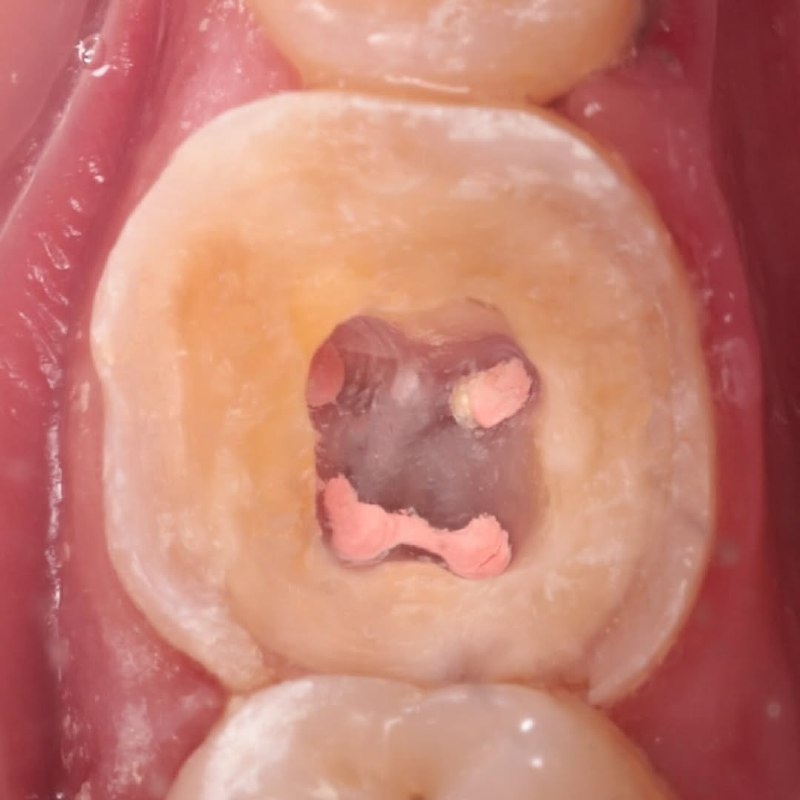

Мужчина обратился по ДМС. Жалобы: ночью разболелась десна и зуб, боль стала отдавать в ухо и висок. Клиент осмотрел зубы и заметил, что один из них потемнел. Принял обезболивающее, боль немного стихла. Однако утром, во время завтрака, было больно пить холодную воду и жевать.

Что сделал стоматолог:

• Визуальный осмотр + рентген больного зуба

• Удаление пульпы

• Инструментальная и медикаментозная обработка каналов

• Установка временной пломбы

• Запись на повторный приём через 3 дня (для установки постоянной пломбы)